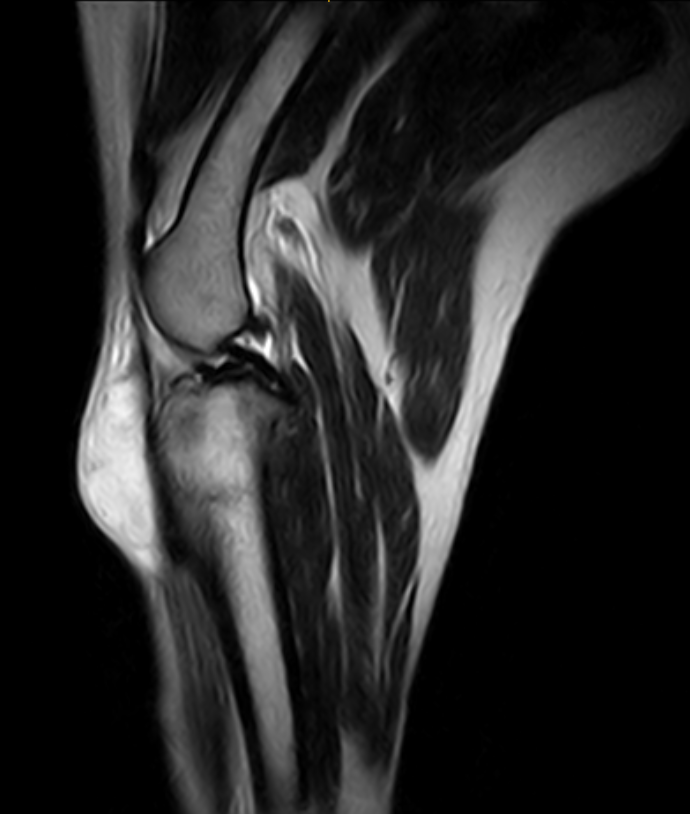

Imágenes de Calidad Premium

VET MR GRANDE

IMÁGENES CLÍNICAS

En la sección de imágenes clínicas, destacamos la precisión y claridad de nuestros estudios, respaldados por un equipo de radiólogos especializados en medicina veterinaria. Nos enorgullece ser un aliado confiable para veterinarios y clínicas, brindando un servicio rápido y eficiente para ayudar en la toma de decisiones clínicas fundamentadas.

Utilizamos resonancia magnética para obtener imágenes detalladas de tejidos blandos, articulaciones y el sistema nervioso central, permitiendo diagnósticos más precisos.